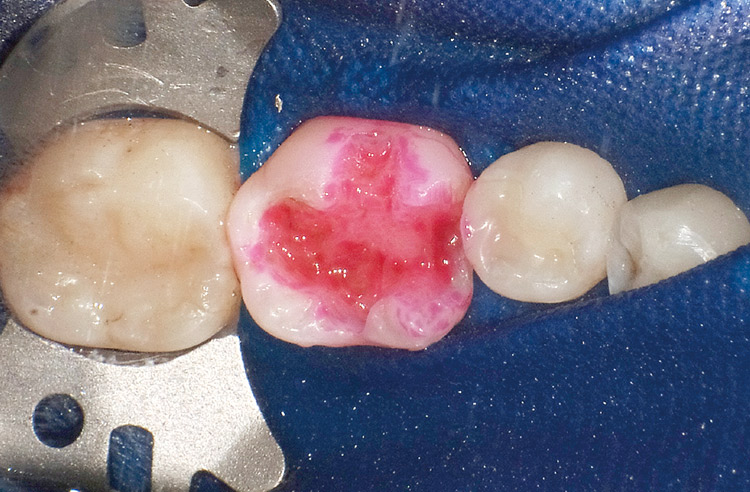

3. う蝕象牙質の検知。う蝕検知液(カリエスディテクター:クラレノリタケデンタル)により、感染象牙質を染色する(図19)。

図19 う蝕象牙質の検知

う蝕検知液(カリエスディテクター)による感染象牙質の染色。